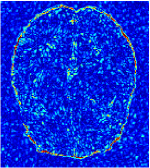

In general supervised learning, training data need to be in the same or similar distribution, heterogeneous data exhibits different structure variations of features which hinders CNNs to extract features efficiently. In our experiments, raw measurements sampled from different ratios of compressed sensing display different levels of incompleteness, these undersampled measurements do not fall in the same distribution but they are related. Different sampling masks are shown at the bottom of Figure 1 and 2 may have complemented sampled points, in the sense that some of the points which sampling ratio mask does not sample have been captured by other masks. In our experiment, different sampling masks provide their own information from their sampled points so that four reconstruction tasks help each other to achieve an efficient performance. Therefore, it explains the reason that Meta-learning is still superior to conventional learning when the sampling ratio is large.

Qualitative comparison between conventional and Meta-learning methods are shown in Figure 1 and 3, which display the reconstructed MR images of the same slice for T1 and T2 respectively, we label the zoomed-in details of HGG in the red boxes. We observe the evidence that conventional learning is more blurry and lost sharp edges, especially in lower CS ratios. From the point-wise error map, we find meta-learning has the ability to reduce noises especially in some detailed and complicated regions comparing to conventional learning.